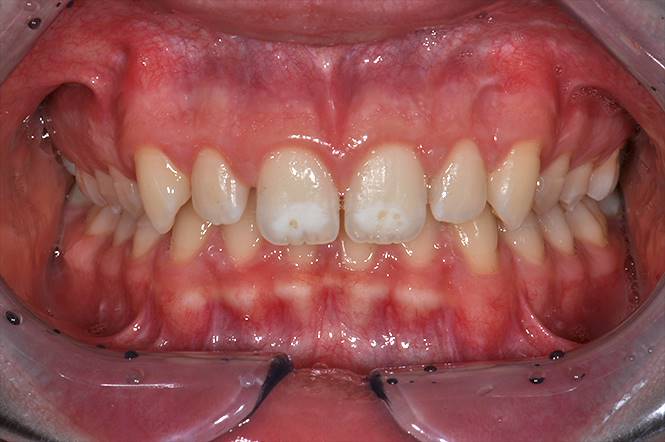

Giulio è stato trattato con apparecchio fisso multibrackets superiore ed inferiore per 24 mesi circa.

Gli obbiettivi del trattamento sono stati quelli di risolvere la II classe molare e canina dx e sn (fig. 3 e 4) ed il morso profondo (fig.2).

Si notino la perfetta I classe molare e canina dx e sn (fig. 7 e 8) e l’arcata a fine trattamento (fig. 6).